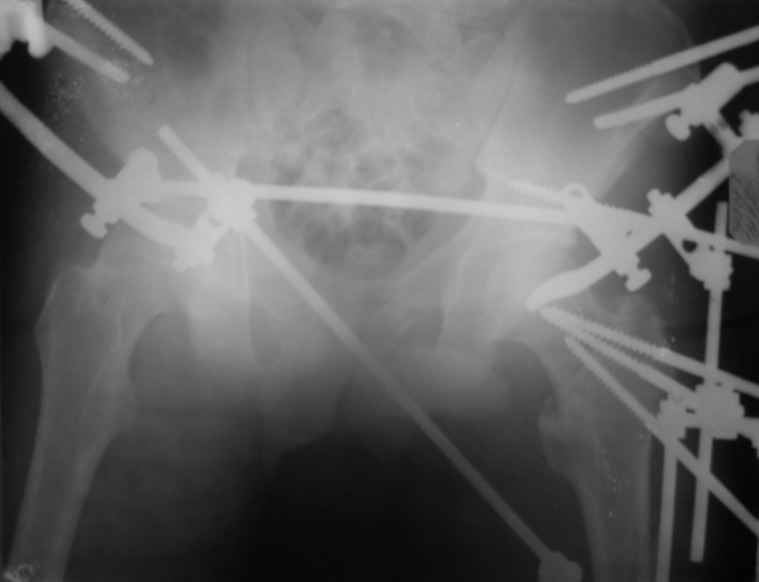

Вот снимки по свежей ситуации, парень 19 лет, длинный оскольчатый

перелом бедра от шейки до в-с/3. давно уже ходит на своих ногах.

Кстати, если тазобедренный сустав безнадежно потерян, то можно по

выведении длины и оси зафиксировать в аппарате дистальный отломок и

только левую половину таза, освободив правую.

Опять же, раз сустав потерян, то открывается свобода ввести

дополнительно стержень в тазовой подсистеме хоть через

шейку-головку-вертлужку. Либо всё-таки над суставом. А ввести его

надо, весьма заметно добавляет стабильности. Так делаем не только мы,

видел снимки в Кургане.